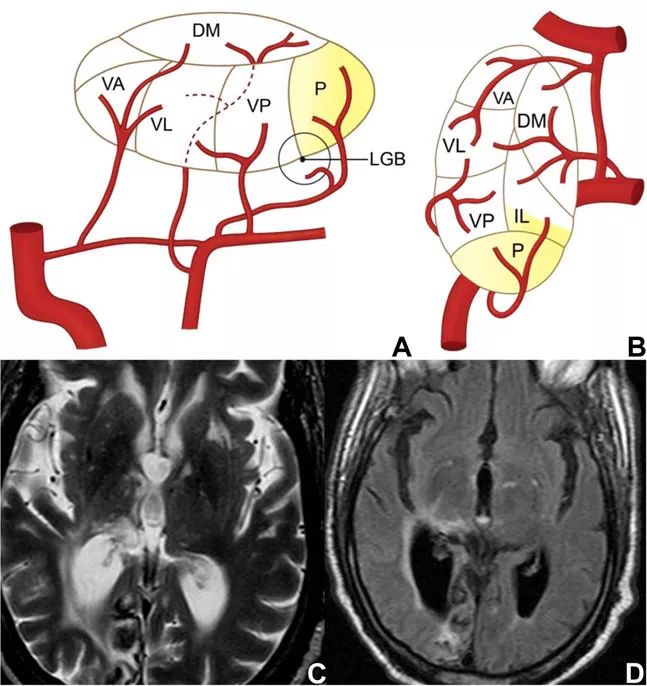

图8 脉络膜后动脉供血示意图和梗死影像学表现

该部位由脉络膜后动脉供血。脉络膜后动脉也来自PCA的P2段,同样是一组小血管组成。目前关于该部位梗死的报道数量仍然有限,在已有的报道中,最常见的症状为象限盲,可能伴有偏身感觉丧失,也可能存在皮质性失语和记忆障碍。

脉络膜后动脉梗死的一项特征性表现为眼球运动障碍,这不是丘脑梗死特有的症状,并且相对较少出现。除此之外,患者还可能表现为迟发性的复杂运动过度综合征,包括共济失调、震颤、肌张力障碍、肌阵挛和舞蹈病等。